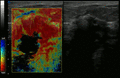

يشير فحص سرطان الثدي إلى اختبار النساء اللائي يتمتعن بصحة جيدة لسرطان الثدي في محاولة لتحقيق تشخيص مبكر على افتراض أن الاكتشاف المبكر سيحسن النتائج. تم استخدام عدد من اختبارات الفحص بما في ذلك الفحص السريري والذاتي فحوصات الثدي وتصوير الثدي والفحص الجيني والموجات فوق الصوتية والتصوير بالرنين المغناطيسي.

يتضمن الفحص السريري أو الذاتي للثدي تحسس الثدي للوقوف على وجود كتل أو أي تشوهات أخرى. يتم إجراء فحوصات الثدي السريرية من قبل مقدمي الرعاية الصحية، بينما تُجرى فحوصات الثدي الذاتية من قبل الشخص نفسه.[109] لا تدعم الأدلة فعالية أي من نوعي فحوصات الثدي، لأنه بحلول الوقت الذي يصبح فيه الورم كبيرًا بما يكفي ليتم اكتشافه، من المحتمل أن ينمو لعدة سنوات وبالتالي يصبح كبيرًا بما يكفي ليتم لاكتشافه بدون فحص.[110][111] يستخدم فحص التصوير الإشعاعي لسرطان الثدي بالأشعة السينية لفحص الثدي بحثًا عن أي كتل. أثناء الفحص، يتم ضغط الثدي ويلتقط الفني صورًا من زوايا متعددة. يلتقط التصوير الشعاعي للثدي العام صورًا للثدي بأكمله، بينما يركز تصوير الثدي الشعاعي التشخيصي على كتلة معينة أو منطقة معينة مثيرة للقلق.[112]

يمكن أن توفر طريقتا الفحص الأكثر شيوعًا، وهما الفحص البدني للثدي بواسطة مقدم الرعاية الصحية والتصوير الإشعاعي للثدي، احتمالًا تقريبيًا لوجود كتلة سرطانية، وقد تكتشف أيضًا بعض الآفات الأخرى، مثل الكيسات البسيطة.[122] عندما تكون هذه الفحوصات غير حاسمة، يمكن لمقدم الرعاية الصحية أخذ عينة من السائل الموجود في الكتلة لتحليلها مجهريًا (إجراء يُعرف باسم الخزعة بالإبرة) للمساعدة في تحديد التشخيص. يمكن إجراء الخزعة بالإبرة في عيادة أو مكتب مقدم الرعاية الصحية. يمكن استخدام مخدر موضعي لتخدير أنسجة الثدي لمنع الألم أثناء العملية، ولكن قد لا يكون ضروريًا إذا لم يكن الورم تحت الجلد. إن اكتشاف وجود سائل واضح يجعل الكتلة غير سرطانية إلى حد كبير، ولكن قد يتم إرسال السائل الدموي للفحص تحت المجهر بحثًا عن الخلايا السرطانية. يمكن استخدام الفحص البدني للثدي، والتصوير الشعاعي للثدي، والخزعة بالإبرة معاً لتشخيص سرطان الثدي بدرجة جيدة من الدقة.

تشمل الخيارات الأخرى لأخذ الخزعة الخزعة الأساسية أو vacuum-assisted breast biopsy،[123] وهي الإجراءات التي يتم فيها إزالة جزء من كتلة الثدي؛ أو الخزعة الاستئصالية، حيث يتم إزالة الورم بأكمله. غالبًا ما تكون نتائج الفحص البدني من قبل مقدم الرعاية الصحية والتصوير الشعاعي للثدي والاختبارات الإضافية التي يمكن إجراؤها في ظروف خاصة (مثل التصوير بواسطة الموجات فوق الصوتية أو التصوير بالرنين المغناطيسي) كافية لتبرير الخزعة الاستئصالية كطريقة تشخيصية وعلاجية أولية.[124][بحاجة لمصدر غير رئيسي]